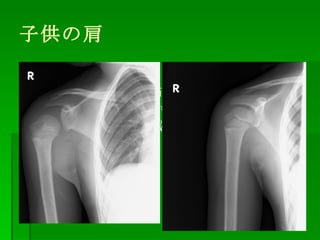

子供 肩 脱臼-脱臼は、どのような時に起こりやすいのか? 肩や肘の関節の脱臼は、転倒やスポーツなどの運動をしている時に、過度の負荷がかかった場合に、脱臼することがあります。 具体的には、 転倒した時に、腕をのばして手をついた時肩を触ると、肩鎖関節あたりに強い痛みがあり、同部が突出しています。 外観上は「肩鎖関節脱臼」を示唆する所見です。 レントゲン像を示します。 レントゲン上も骨折線などはなく、典型的な肩鎖関節脱臼として矛盾しない所見です。